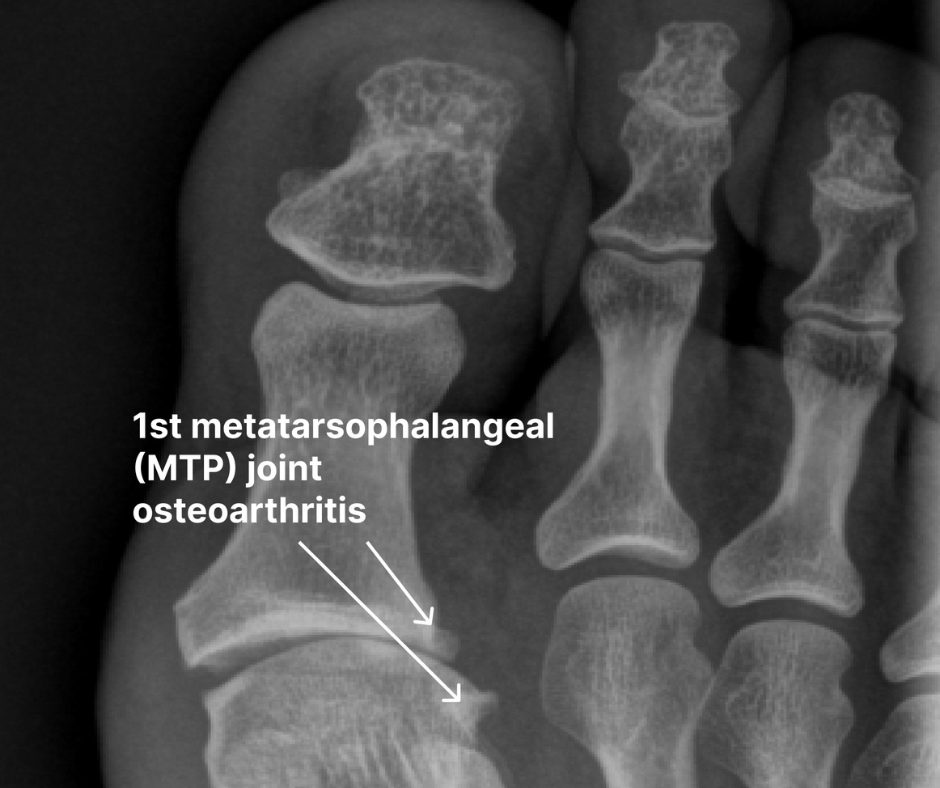

Hallux limitus and hallux rigidus are related degenerative joint conditions that affect the metatarsophalangeal joint of the big toe. Hallux limitus is the earlier stage of osteoarthritis characterized by reduced range of motion in the MTP joint, particularly during extension. Common signs and symptoms include mild pain, especially on top of the toe joint, stiffness, the development of a callus under the big toe, and difficulty flexing or extending the toes.

Hallux rigidus is the advanced stage of joint degeneration, where the joint becomes rigid and immovable. This osteoarthritis of the big toe causes joint space narrowing, cartilage loss, bone spurring, and persistent pain, even at rest. Researchers estimate that hallux rigidus affects about 26.7% of people over 50.3